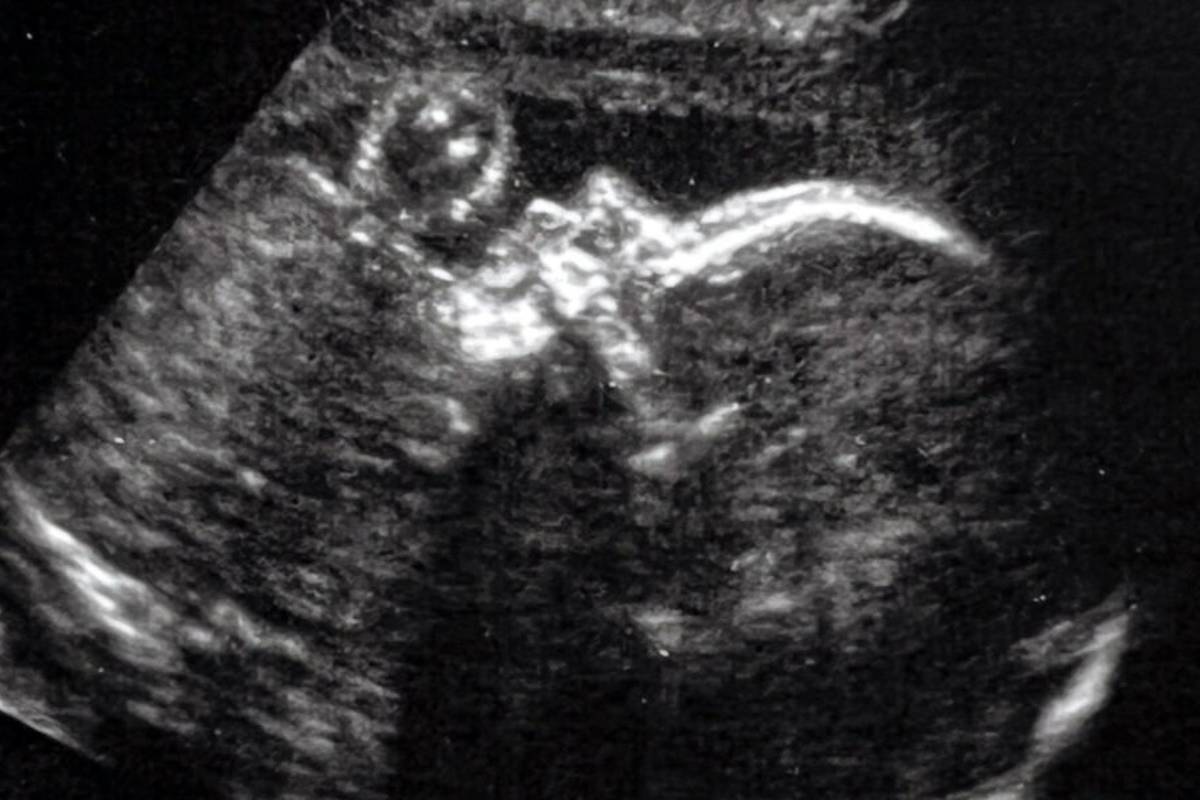

جراحان «بیمارستان کودکان بوستون» و «بیمارستان Brigham and Women» با کمک اولتراسوند، از یک روش جراحی به نام «آمبولیزاسیون» (Embolization) برای درمان یک بیماری نادر قبل از تولد استفاده کردند. این بیماری که از آن بهعنوان «ناهنجاری ورید جالینوس» یاد میشود، به خون اجازه میدهد تا پس از تولد کودک، به طرز خطرناکی در بخشی از مغز جریان پیدا کند.

بیمار این پرونده یک جنین 34 هفتهای بوده (دوره کامل حدود 40 هفته است) که برای اولین بار طی یک دوره سونوگرافی معمولی در هفته 30 خود، مشخص شده بود دارای ناهنجاری مغزی است. اورباخ در ادامه درباره وضعیت این نوزاد میگوید: